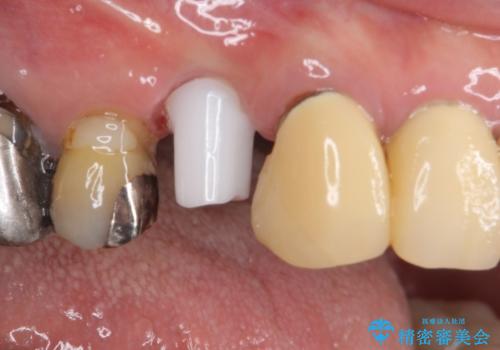

ジルコニアカスタムアバットメントは、歯肉ラインに金属が見えにくいというだけでなく、クラウンを装着する土台の形が天然歯と近い形態となるため、清掃性が高く歯肉が腫れにくいというメリットがあります。